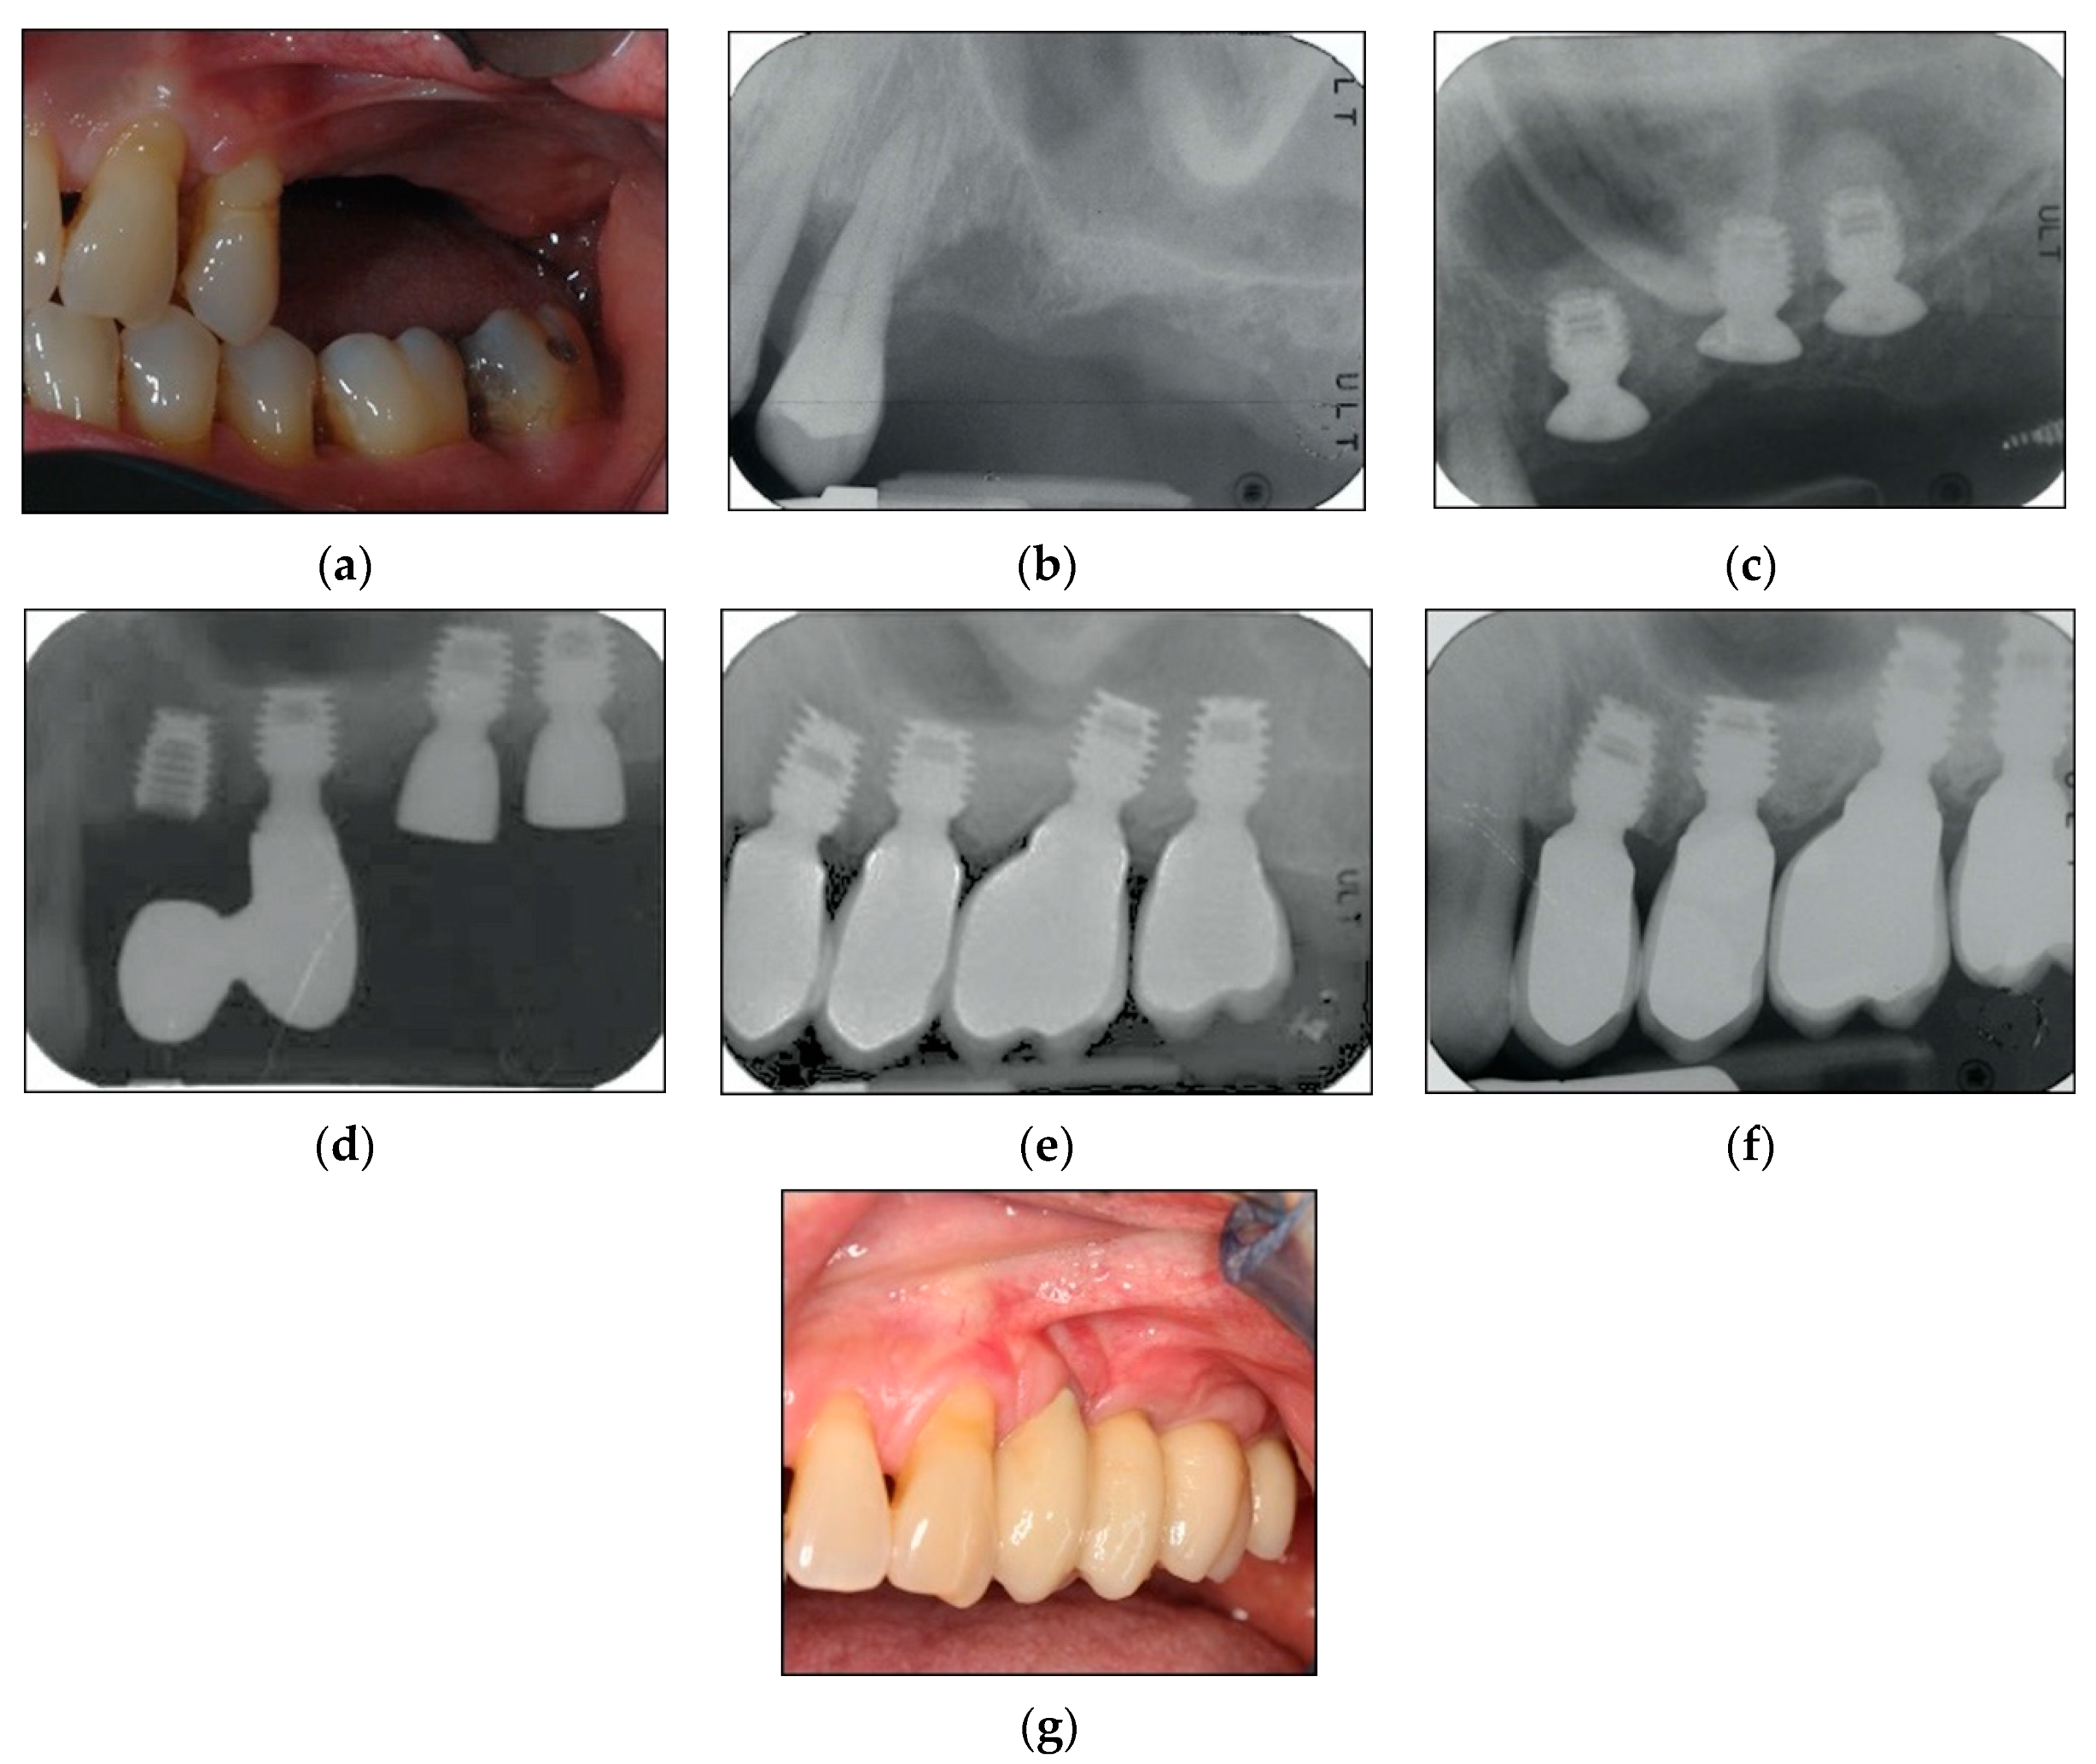

A maintenance program was designed to provide patients a professional oral hygiene session every four months [33] and home care procedures were reinforced. At each recall appointment, occlusion was assessed and adjusted as necessary; prosthetic restorations were checked for loosening, chipping, or other types of complications. Clinical assessment of peri-implant soft tissues and radiographic examinations were performed after three years of follow-up from loading time [29,30]. By way of illustration, Figure 2, Figure 3 and Figure 4 report some radiographic cases.

Figure 2. (af). Clinical case: Single implant placed in 1.6 site. (a) Clinical photograph before implant placement, missing first molar. (b) Pre-operative radiograph before implant placement in site 1.6. See minimal bone in implant site. (c) Radiograph obtained at implant placement. See short implant with sinus lift temporary abutment designed to prevent displacement of the implant into the sinus, also see augmented sinus floor. (d) Radiograph obtained at time of loading. See augmented sinus floor, also see the radiolucent area in the crown of the second bicuspid, which was a lost restoration. (e) Radiograph obtained at three-year follow-up. See stable bone levels, also see the replaced restoration in the crown of the second bicuspid. (f) Clinical photograph at three-year follow-up. See stable clinical conditions.